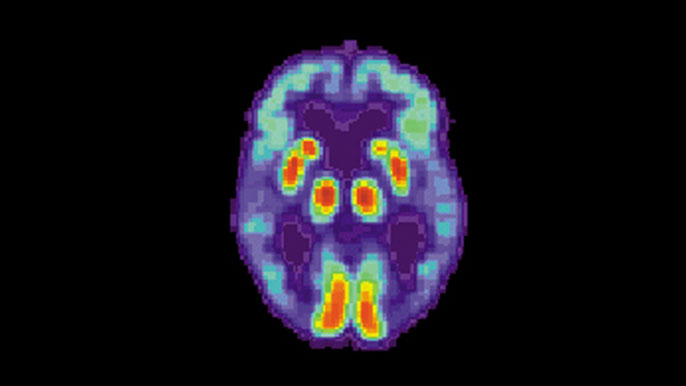

Positron emission tomography (PET) scans, which measure the levels of specific molecules, like glucose, in the brain, have been investigated as one tool to help diagnose Alzheimer’s disease before the symptoms become severe. Glucose is the primary source of fuel for brain cells, and the more active a cell is, the more glucose it uses. As brain cells become diseased and die, they use less and, eventually, no glucose.

Other types of PET scans look for proteins specifically related to Alzheimer’s disease, but glucose PET scans are much more common and cheaper, especially in smaller health care facilities and developing countries, because they’re also used for cancer staging.

Radiologists have used these scans to try to detect Alzheimer’s by looking for reduced glucose levels across the brain, especially in the frontal and parietal lobes of the brain. However, because the disease is a slow progressive disorder, the changes in glucose are very subtle and so difficult to spot with the naked eye.

Credit: UCSF